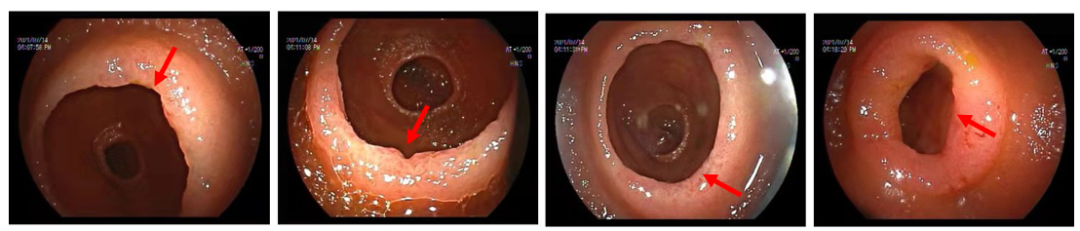

图2 经肛小肠镜检查发现空肠远端及近段回肠多发环形狭窄,散在糜烂及不规则溃疡,溃疡最大径约0.8 cm,呈横向分布。

关键检查揭晓: 经肛小肠镜检查发现空肠远端及近段回肠多发环形狭窄,散在糜烂及不规则溃疡,溃疡最大径约0.8 cm,呈横向分布。活检病理示:检材零碎的小肠黏膜,局灶绒毛稍圆钝及隐窝延长,偶见分支,间质水肿,未见明显肉芽肿及非干酪样坏死。